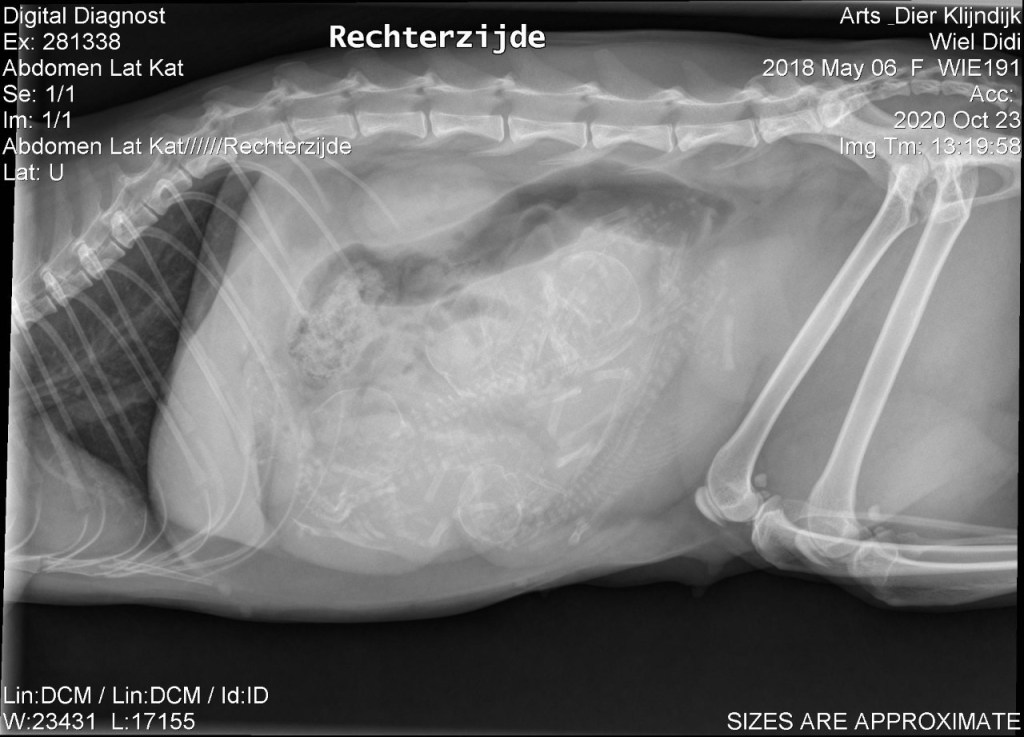

Inmiddels zijn we alweer op dag 58 en hebben we een paar dagen geleden een röntgenfoto laten maken om te zien hoe druk het wordt.